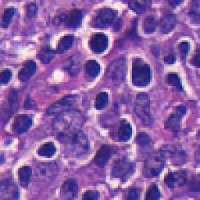

Medical Diagnostics & Research: Researchers and healthcare providers can use LDANN-BASIC to assist in the identification of lymphocyte classes, helping to diagnose diseases like leukemia or lymphoma more efficiently and enhancing our understanding of the immune system.

Pharmaceutical Development & Drug Testing: The model can be employed in pharmaceutical labs to study the effects of new drugs on lymphocyte populations, contributing to the development of more effective medications or therapies targeting specific immune conditions.

Automated Clinical Laboratory Systems: LDANN-BASIC can be integrated into automated image analysis workflows within clinical laboratories, streamlining the process of analyzing patient samples and reducing the risk of human error in lymphocyte classification.

Educational Purposes: The model can serve as a teaching tool for medical students, clinical laboratory scientists, and immunology researchers to learn and visually understand different types of lymphocytes, thereby improving their skills and knowledge in the field of histology and pathology.

Remote and Telemedicine Diagnostics: LDANN-BASIC can be used in remote healthcare settings or telemedical diagnostic systems, enabling healthcare professionals to analyze blood samples from patients even if they are located in rural or remote areas with limited access to specialized labs.